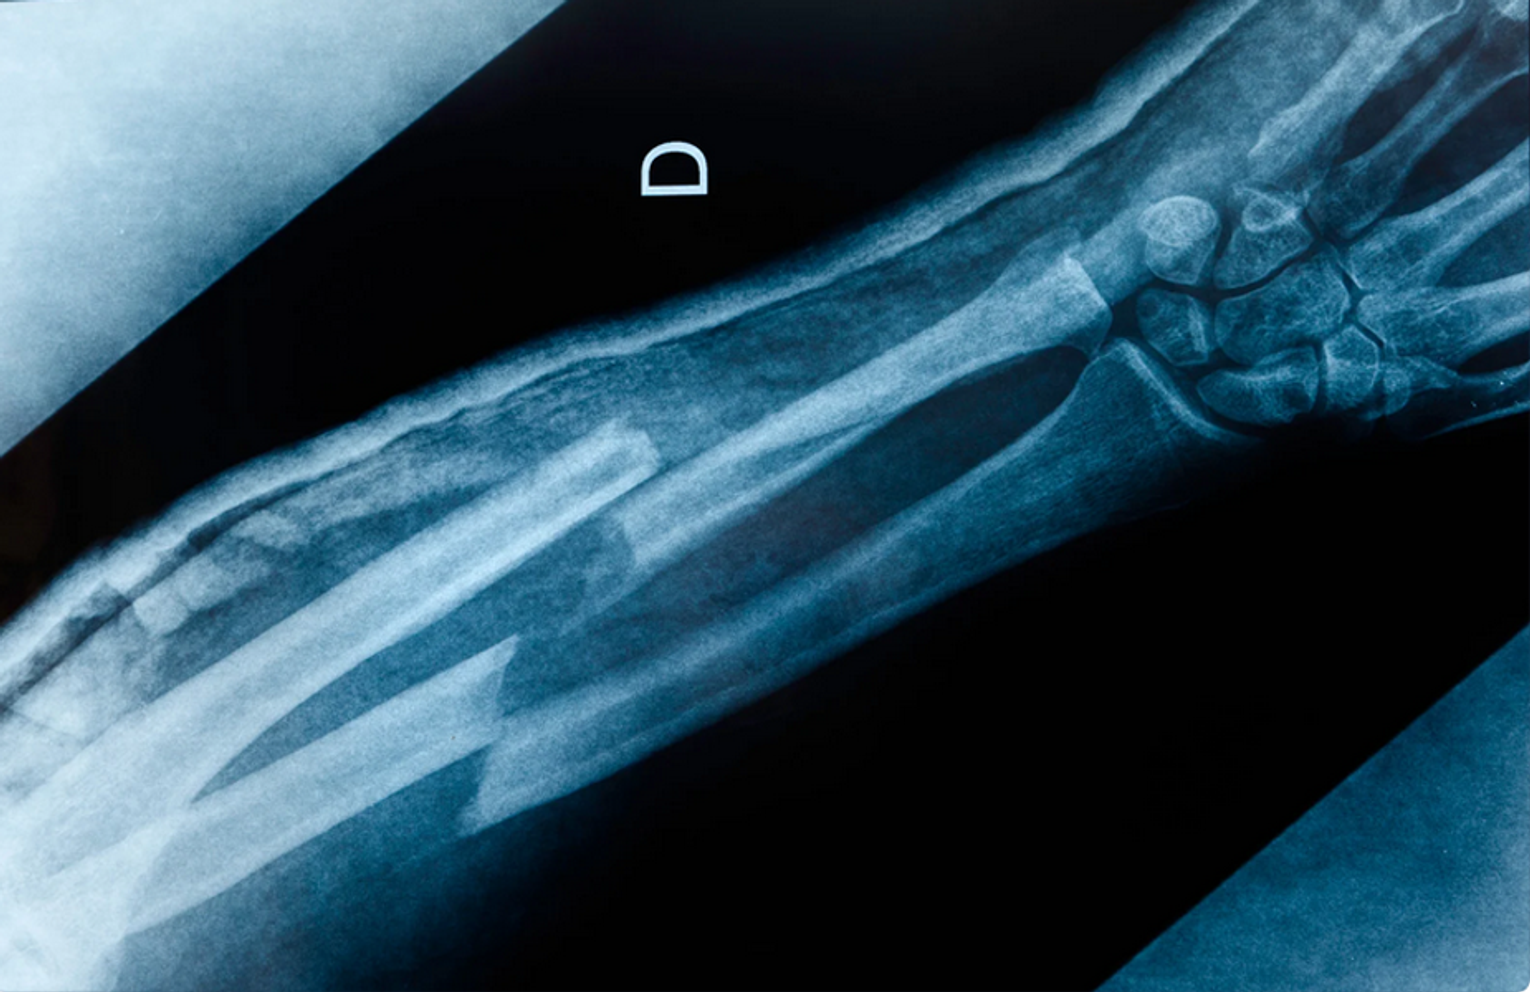

Z danych statystycznych wynika, że w styczniu 2026 r. na SOR zgłosiło się w sumie 3631 pacjentów, z czego 758 osób miało urazy spowodowane głównie trudnymi warunkami komunikacyjnymi. Były to przede wszystkim złamania (302), stłuczenia (278) i zwichnięcia (44). Natomiast między 1 a 8 lutego, a więc wraz z nastaniem gołoledzi i marznących opadów deszczu, w SOR udzielono pomocy 1172 osobom, w tym 786 miało urazy. Najwięcej było złamań (344) i stłuczeń (312), a także zwichnięć (32).